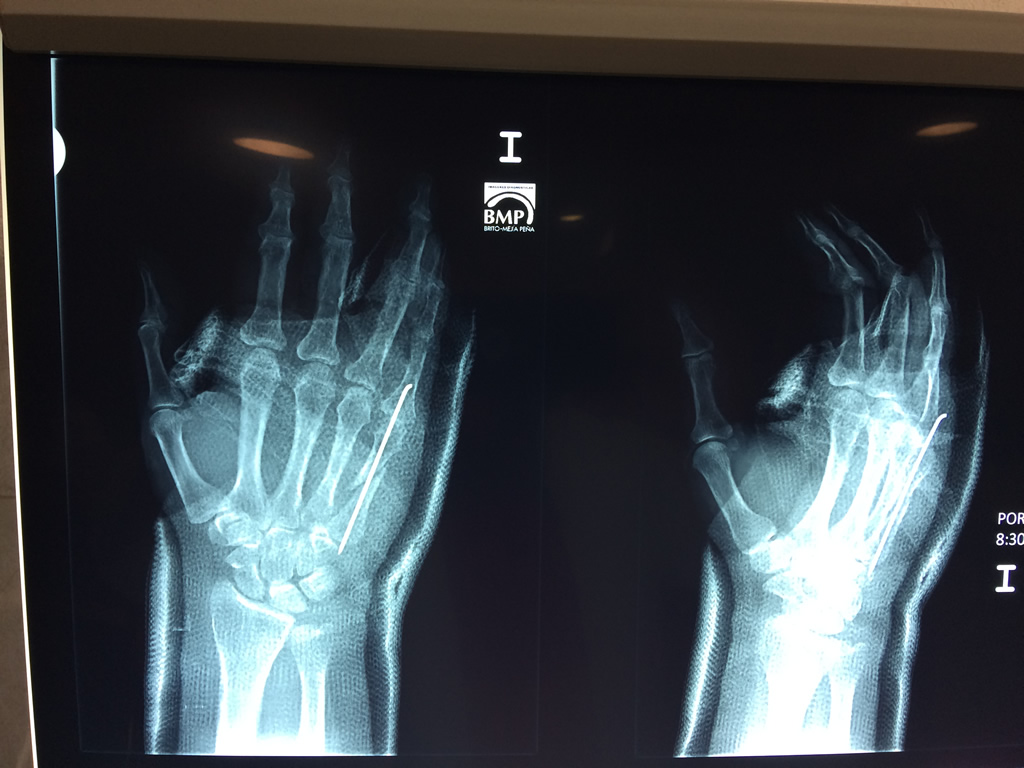

Cirugía de Fémur - Cirugías de Muñecas y Manos

Los procedimientos más comunes en cirugía de la mano son aquellos destinados a reparar traumatismos, incluyendo lesiones de tendones, nervios, vasos sanguíneos, y articulaciones; huesos fracturados; y quemaduras, cortes, y otros daños de la piel.